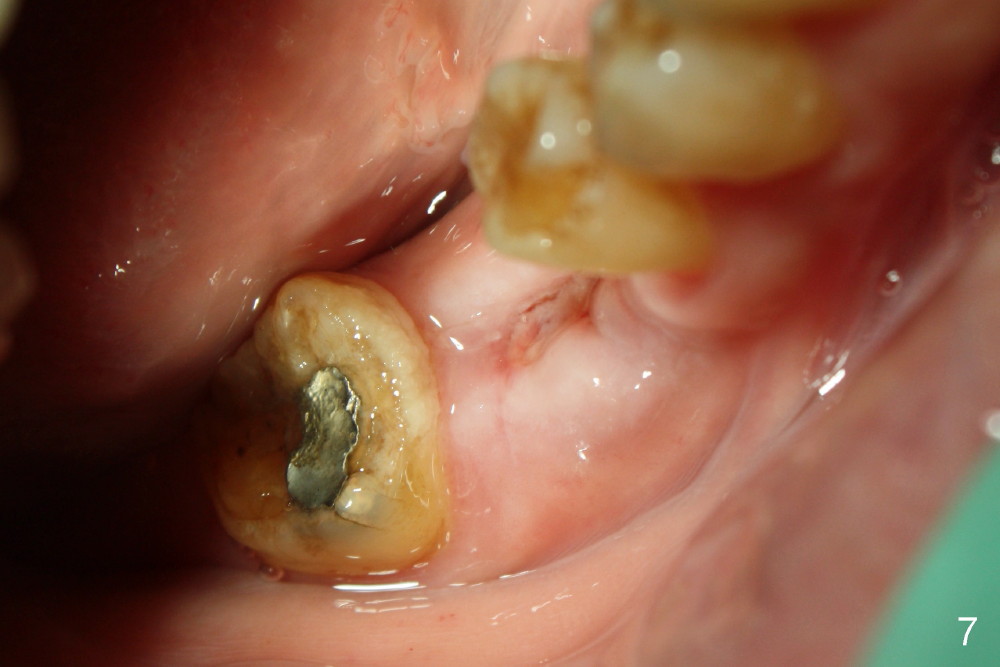

The tooth #30 was extracted in other office 1 month ago. The socket appears to heal normally. A tissue-level implant is placed as planned and smoothly. No antibiotic is prescribed pre- or post-op. The patient reports mild pain 1 week postop. There is a sign of infection. Amoxicillin is prescribed. One week later, the symptom improves, but the infection signs are present (Fig.1). The implant has mobility and is removed (Fig.2). The osteotomy is thoroughly debrided, followed by copious irrigation with normal saline and Clindamycin soaking. Irradiated cancellous bone graft (.5 mg) is placed (Fig.3,4). The wound is covered by collagen plug (Fig.5) and sutured with Chromic gut (Fig.6). Amoxicilin is prescribed postop. One week follow up reveals normal wound healing (Fig.7 (buccal view), 8 (lingual)).